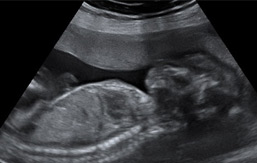

Ecografías de la semana 27 de embarazo

Ecografía semana 27: corte sagital del feto. Podemos ver la cabeza del bebé a la derecha. Se visualiza diafragma que separa cavidad torácica de la abdominal. En la parte superior del diafragma, visualizamos corazón y pulmones; en la parte inferior de dicho órgano, hígado y estómago.